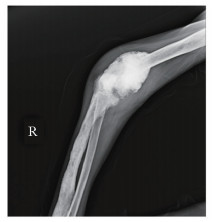

• 摘要: SAPHO综合征是一类以骨关节和皮肤病变为特点的罕见临床综合征,即出现滑膜炎(synovitis)、痤疮(acne)、脓疱病(pustulosis)、骨肥厚(hyperostosis)和骨炎(osteitis)等一系列病变。本文报道一例具有31年病史的非典型SAPHO综合征患者,经详细的诊断及鉴别诊断以及合理的诊疗方案的实施,最终患者病情获得明显改善。通过回顾并总结SAPHO综合征的临床诊疗特点,以及对该病例的讨论分析过程,充分体现了多学科诊疗在罕见病诊治中的有效性及必要性。

Abstract: The SAPHO syndrome is a rare disease characterized by osteoarticular and dermatological manifestations. Here we reported an atypical case of SAPHO syndrome for 31 years. A multidisciplinary team made the diagnosis and differential diagnosis of the patient's osteoarticular and dermatological lesions. Subse-quently, suitable treatment was initiated and the patient's condition was significantly improved. At last, we reviewed and sum- marized the characteristics of diagnosis and treatment of SAPHO syndrome. The effectiveness and necessity of multidisciplinary treatment were demonstrated by the discussion and analysis of this rare disease.